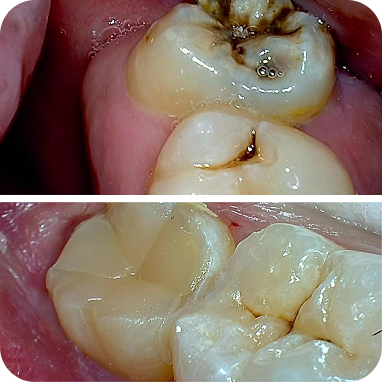

Pengalaman aku setelah melakukan scaling dan beberapa tindakan lain. Semua tindakan berjalan dengan baik, dokternya juga oke banget. Kebetulan ditangani dengan drg. Safira, aku baru ini tambal gigi minim rasa ngilu. Kalian tidak usah ragu kalau ke Dharmawangsa Dental Studio!